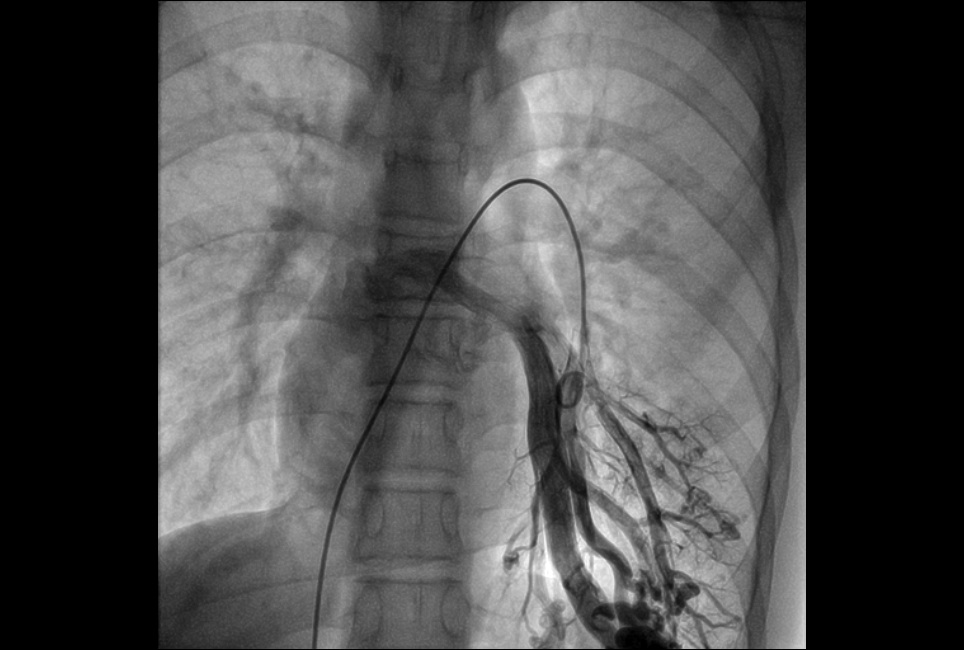

2.外周血管介入手术治疗:腹主动脉血管病症,肝脏肿瘤治疗,肝脏,肺部肿瘤活检,椎体成形术,泌尿系统血管病变等微创介入手术。

DSA造影显示肝癌 通过微导管栓塞病灶,阻断了肿瘤供血,肿瘤逐渐萎缩

左下肺动脉造影 右下肺动脉造影 图左:腹主动脉瘤造影 图右:腹主动脉瘤支架植入造影